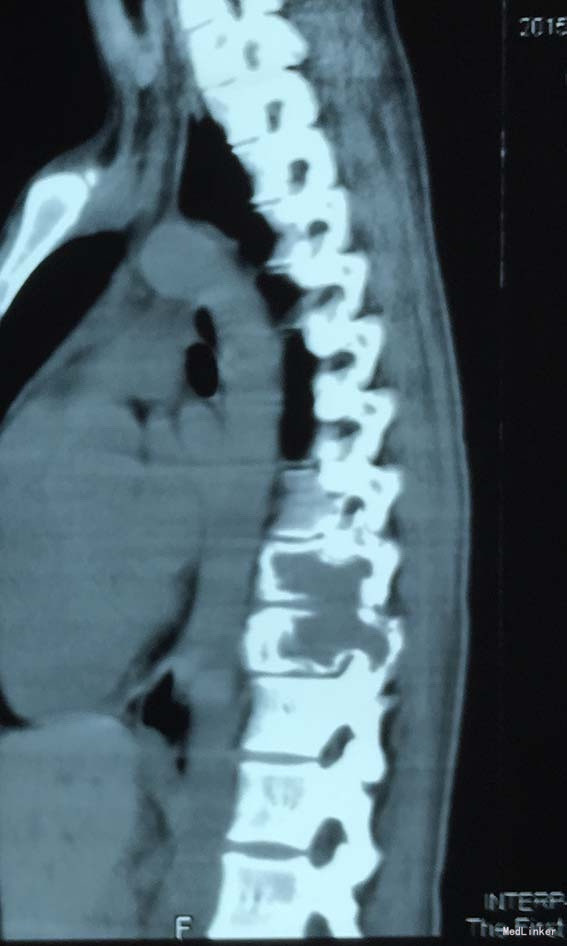

查体:脊柱外观无明显畸形,颈椎活动度正常,胸背部可见纵向长约15cm切口,皮肤钉缝合,伤口愈合可,无红肿渗液。胸椎9-10体左侧棘突旁局部压痛(+)、叩击痛(-),压头试验阴性,双侧侧臂丛牵拉实验(-),双上肢肌张力、运动、感觉及反射无明显异常、躯体感觉无明显减退,双下肢髂腰肌、股四头肌、胫前肌肌力IV级,感觉正常,双下肢直腿抬高试验(-),双侧腱反射对称略活跃,双侧Hoffman征(-),双侧Babinski征(-),双侧髌阵挛(-),踝阵挛(-)。 辅助检查:2015-11外院胸椎MRI检查发现T9-10节段椎体肿瘤并椎旁软组织肿块形成,肿块突入胸腔占位

诊断:胸椎椎体肿瘤(T9-10) 治疗:先于外院行1期后路椎弓根钉固定融合手术,然后转入我院行介入下术前椎体节段血管栓塞手术,第二天行经左侧胸腔入路椎体肿瘤病灶刮除并钛网植骨植入重建手术。术后恢复满意。复查MRI显示肿瘤病灶基本完全切除。